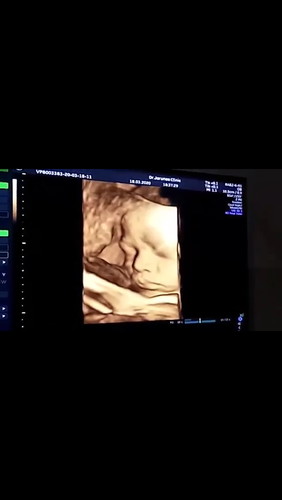

หนูน้อย 30 weeks

เห็นหน้าชัดจังเลยค่ะ อิจฉาจังบ้านนี้ตอน30วีคน้องเอามือสองข้างปิดหน้าไว้ไม่ให้เห็นเลยค่ะ หนีบขาด้วยค่ะเห็นแต่ไข่ห้อยลงมา😂หมอบอกให้ลุ้นอีกทีตอน32วีคว่าเค้าจะให้ดูหน้ามั้ย